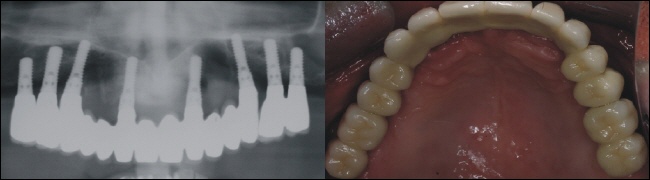

Versorgung - festsitzende Brücke

Das Röntgenkontrollbild oben links zeigt den exakten Sitz der Brückenkonstruktion. Oben rechts sieht man die einzementierte Brücke im Mund. Die Versorgung ist nur auf den Kieferkamm begrenzt, das heiß der ganze Gaumen ist frei. Dies bietet höchsten Komfort und ein ästhetisches Optimum, ganz so wie bei den eigenen Zähnen.